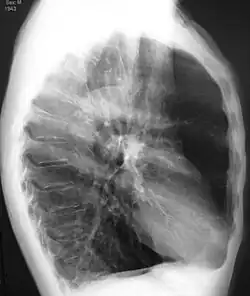

A realização de uma radiografia ao tórax e de um hemograma permitem excluir outras condições no momento do diagnóstico.[69] Os sinais característicos da DPOC observáveis em radiografia são pulmões sobre-expandidos, diafragma achatado e espaço retroesternal aumentado. Ao mesmo tempo, a radiografia permite excluir outras doenças pulmonares, como pneumonia, edema pulmonar ou pneumotórax.[70] Uma tomografia axial computorizada ao tórax permite mostrar a distribuição do enfisema pelos pulmões e pode ajudar a excluir outras doenças pulmonares.[18] No entanto, a não ser nos casos em que se planeie a realização de uma cirurgia, esta distribuição raramente influencia o tratamento.[18] Pode ainda ser realizada uma gasometria arterial para determinar a necessidade de oxigénio suplementar. Este exame é recomendado em pessoas com VEF1 inferior a 35% do previsto, com saturação periférica de oxigénio inferior a 92% e pessoas com sintomas de insuficiência cardíaca congestiva.[17] Em regiões do mundo onde é comum a deficiência de alfa-1 antitripsina, as pessoas com DPOC devem considerar a realização deste exame, sobretudo aquelas com idade inferior a 45 anos e em que o enfisema afeta a parte inferior dos pulmões.[17]

- Radiografia torácica de DPOC grave, em que se observa o tamanho relativamente pequeno do coração em relação aos pulmões.

- Radiografia torácica lateral de pessoa com enfisema, em que se observa tórax em tonel e diafragma achatado.